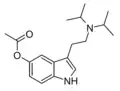

| DiPT | artificial | H | CH(CH3)2 | CH(CH3)2 | N,N-diisopropyltryptamine | 14780-24-6 |